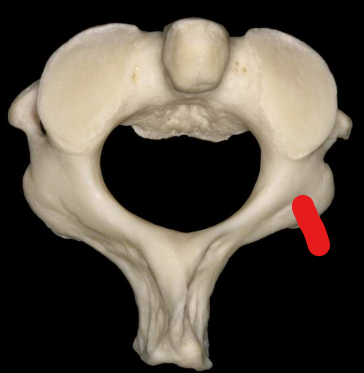

Atlas

Anterior tubercle

Anterior arch

Superior articular facet

Transverse foramen

Posterior arch

Posterior tubercle

Lateral masses